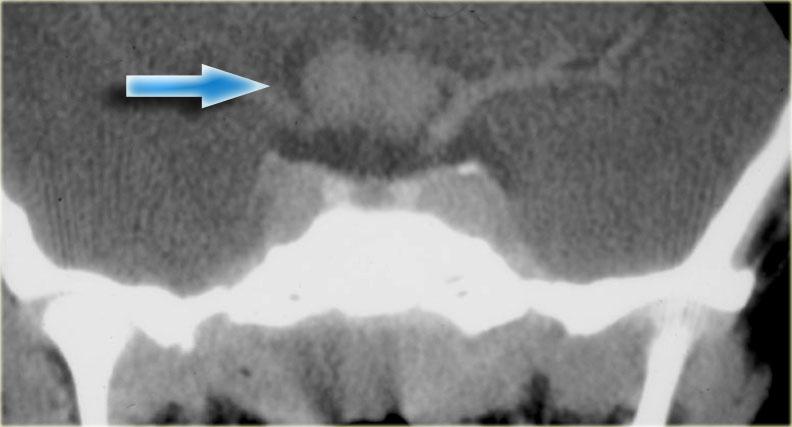

U dây sống (Chordoma)

U dây sống (chordoma) là tổn thương thường gặp nhất tại vùng xương nền (clivus), đây cũng là vị trí ưa thích của di căn và u sụn ác tính (chondrosarcoma).

Bệnh nhân này có tuyến yên bình thường.

Phía sau tuyến yên là một khối lớn dạng sùi, nằm ở vị trí tương ứng xương nền.

Hình ảnh CT cho thấy một số vôi hóa trong vùng này.

Chẩn đoán phân biệt cho khối này bao gồm u dây sống (chordoma) hoặc u sụn ác tính (chondrosarcoma).

U dây sống có xu hướng xuất hiện ở đường giữa, trong khi u sụn ác tính có xu hướng xuất hiện lệch khỏi đường giữa.